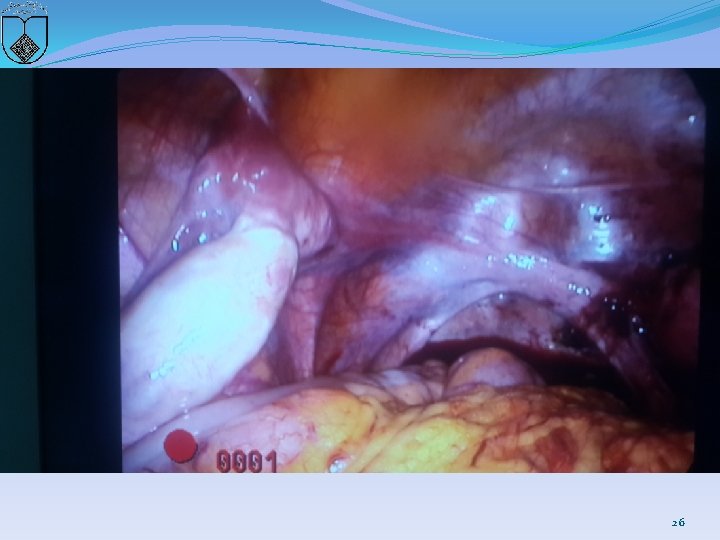

Case 2 � 19 y Married without coitus �C. C: Primary amenorrhea and chronic pelvic pain �Lab test and karyotype was normal �Rectovaginal exam: 3 -4 cm vaginal pouch & don’t touch cervix �Sono: unilateral Rudimentary horn without endometrial line and NL ovaries �MRI: …Cervix was not seen, NL Kidny �Diag Laparoscopy 24

25

26